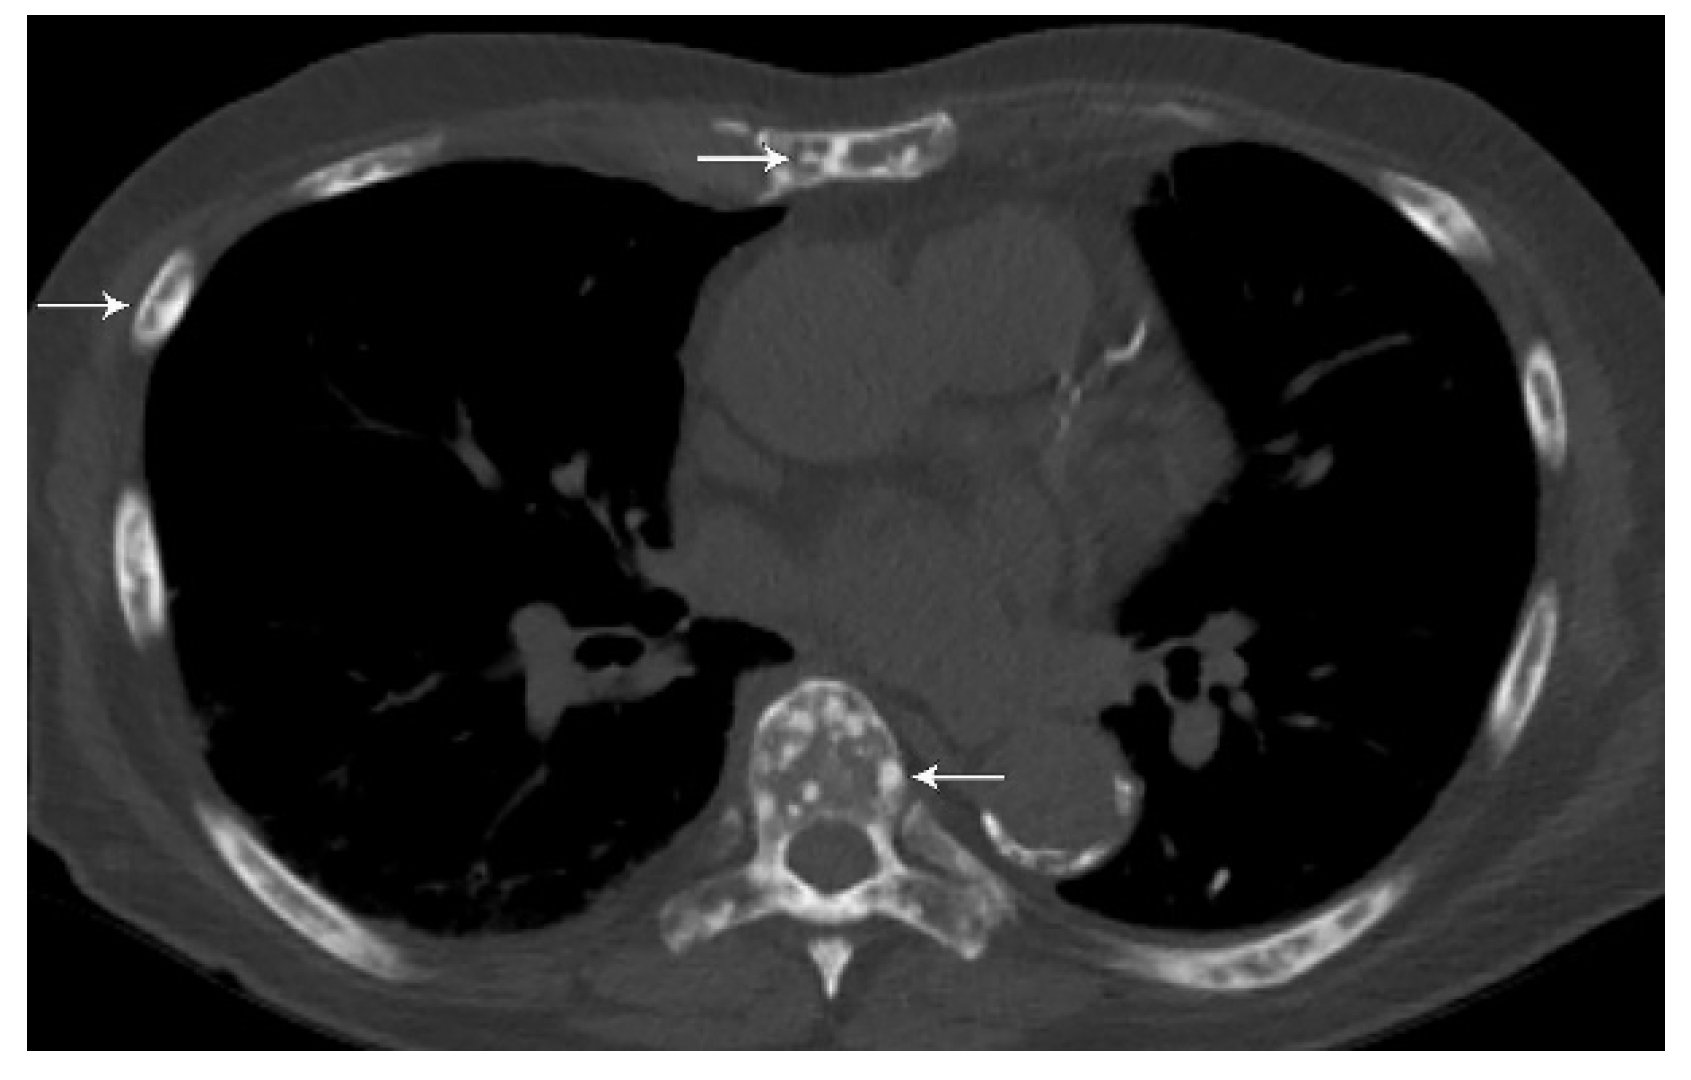

3. N Classification

4. M Classification

- Qu, X.; Huang, X.; Yan, W.; Wu, L.; Dai, K. A meta-analysis of (1)(8)FDG-PET-CT, (1)(8)FDG-PET, MRI and bone scintigraphy for diagnosis of bone metastases in patients with lung cancer. Eur. J. Radiol. 2012, 81, 1007–1015. [Google Scholar] [CrossRef] [PubMed]

- Confavreux, C.B.; Pialat, J.B.; Belliere, A.; Brevet, M.; Decroisette, C.; Tescaru, A.; Wegrzyn, J.; Barrey, C.; Mornex, F.; Souquet, P.J.; et al. Bone metastases from lung cancer: A paradigm for multidisciplinary onco-rheumatology management. Jt. Bone Spine 2019, 86, 185–194. [Google Scholar] [CrossRef]